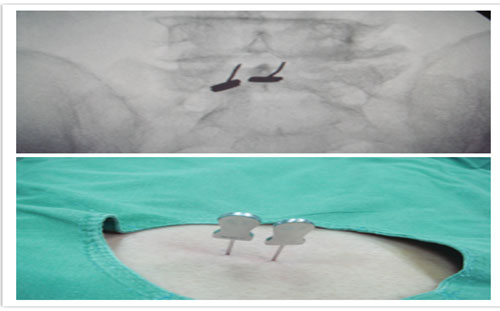

近日,山东大学第二医院疼痛科采用C臂引导下腰椎椎旁小关节内缘入路,行针刀黄韧带松解及侧隐窝注射,治疗老年椎管狭窄症患者,获得了良好疗效。

即“腰椎椎旁小关节内缘入路,用针刀切割松解黄韧带,减轻黄韧带的张力,在后路扩大椎管腔隙;用穿刺针在侧隐窝内注射较大容量的液体(含低浓度麻药和营养神经药物),松解和扩张椎管侧前方腔隙”,使患者的椎管狭窄症得到治疗。

此术式在C臂引导下完成,穿刺过程和到位情况在C臂屏幕上清晰可视,手术时间短、创伤小、安全性高、有效性得到了长期临床验证,适用于不耐受开放性大手术的广大老年腰椎病患者。